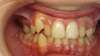

Tel était le cas de notre patiente, après extraction de prémolaires, cette dernière a eu un traitement multibague de façon à pouvoir aligner les dents.

Avant / Après